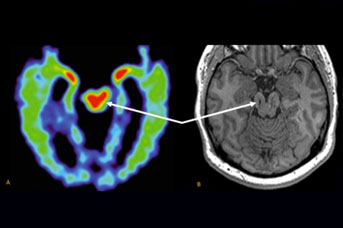

Using a new software tool for analyzing MRI scans, the researchers detected the shrinkage of several key brain regions in a former football player with cognitive problems. The same pattern of brain changes is commonly seen in CTE cases that have been confirmed by autopsies after a person’s death.

The MRI scan did reveal a few small lesions consistent with Smith’s history of brain trauma. Merrill and Raji also used a new FDA-cleared MRI software analysis tool called Neuroreader to measure the volumes of 45 different regions of the patient’s brain.

The analysis revealed abnormally low volumes for Smith’s brainstem, his ventral diencephalon and frontal lobes. The shrinkage in these volumes was worse in the later scan, suggesting a progression of disease. On the whole Smith’s brain lost about 14 percent of its total gray-matter volume (the volume taken up by brain cells, not nerve fibers) during the four-year interval.

Researchers are trying to develop other methods for diagnosing CTE in the living, including PET scans based on radioactive tracers that bind to tau aggregates. But an MRI-based method, which uses no radioactive materials, would be safer and less expensive, Merrill said.